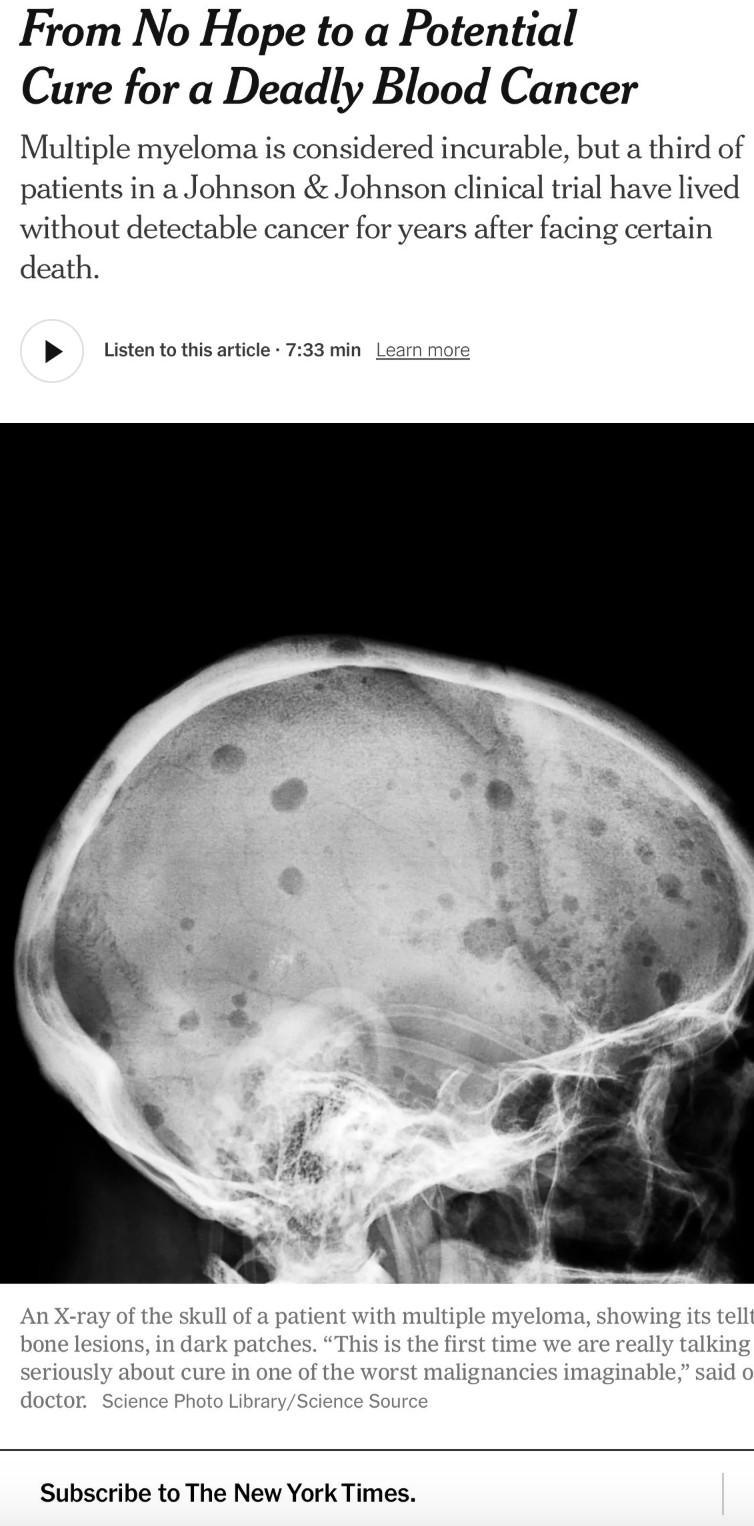

Will these drugs have curative potential in NDMM/Early RRMM!!!

• CARTITUDE-1 (n=97) Accelerated FDA Approval: 2/22/2022. ?? Cure in RRMM